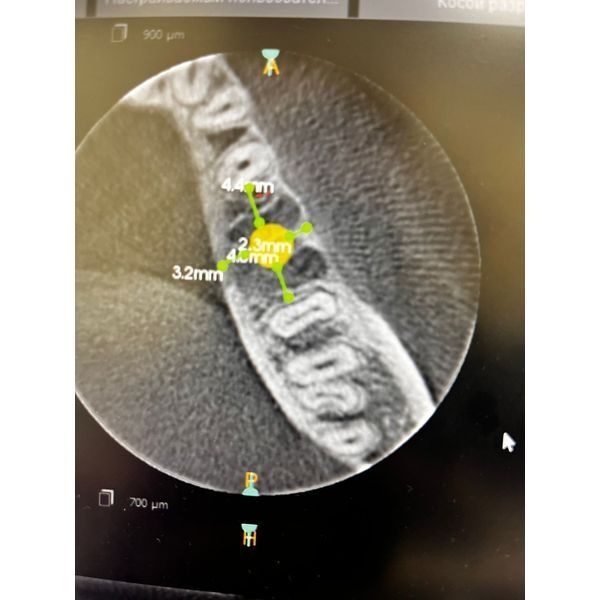

КТ нижней челюсти показала:

- ширина в планируемом месте постановки имплантата приблизительно 10 мм;

- высота до нижнего альвеолярного нерва — 14 мм;

- расстояние между зубами 3.5 и 3.7 — 13 мм.